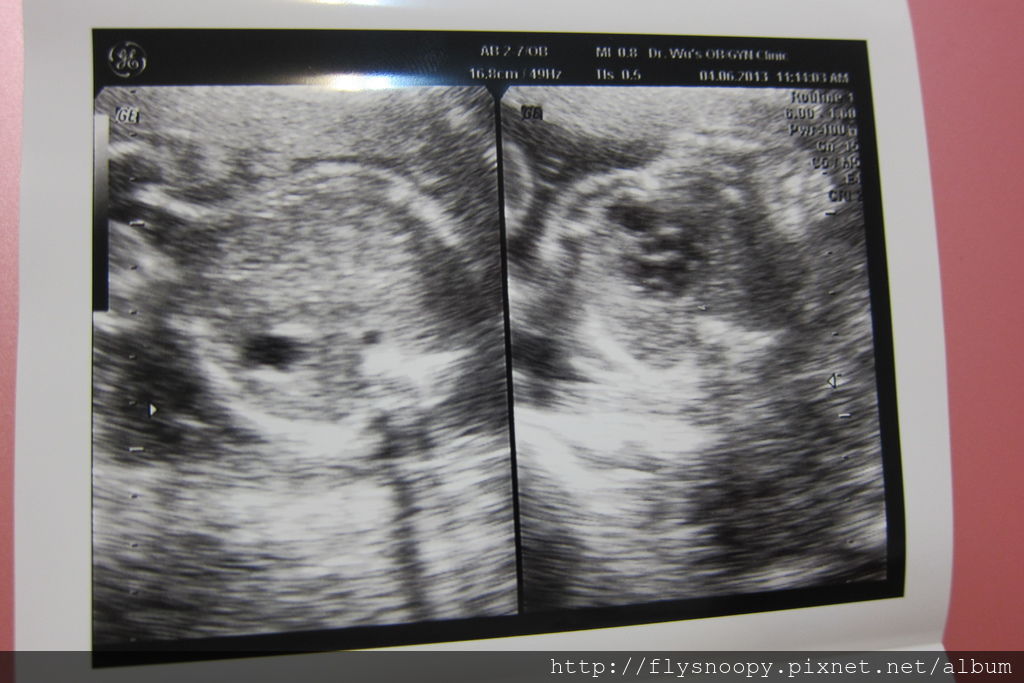

第二張應該一邊是腹腔,一邊是胸腔吧

沒有醫生解釋我就看不懂了